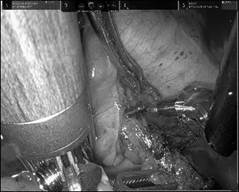

纯单孔机器人肺叶切除术中灵活操作录像剪影

在楔形切除的冰冻病理证实患者患有浸润性肺腺癌后,强光亮主任手术团队开始实施纯单孔达芬奇机器人手术。在手术台上,强光亮主任操作精巧,马善吴、汤继征医生与主刀医生精准配合。林楚童医生则根据前期的探索经验,协助进行机械臂的合理安装,解决机械臂单孔操作下互相妨碍的问题。